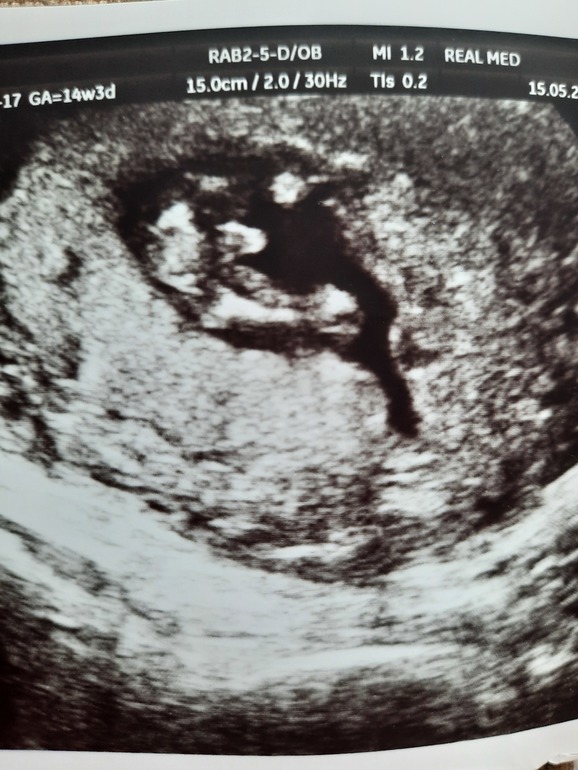

и это наше узи 14 недель 3 дня.